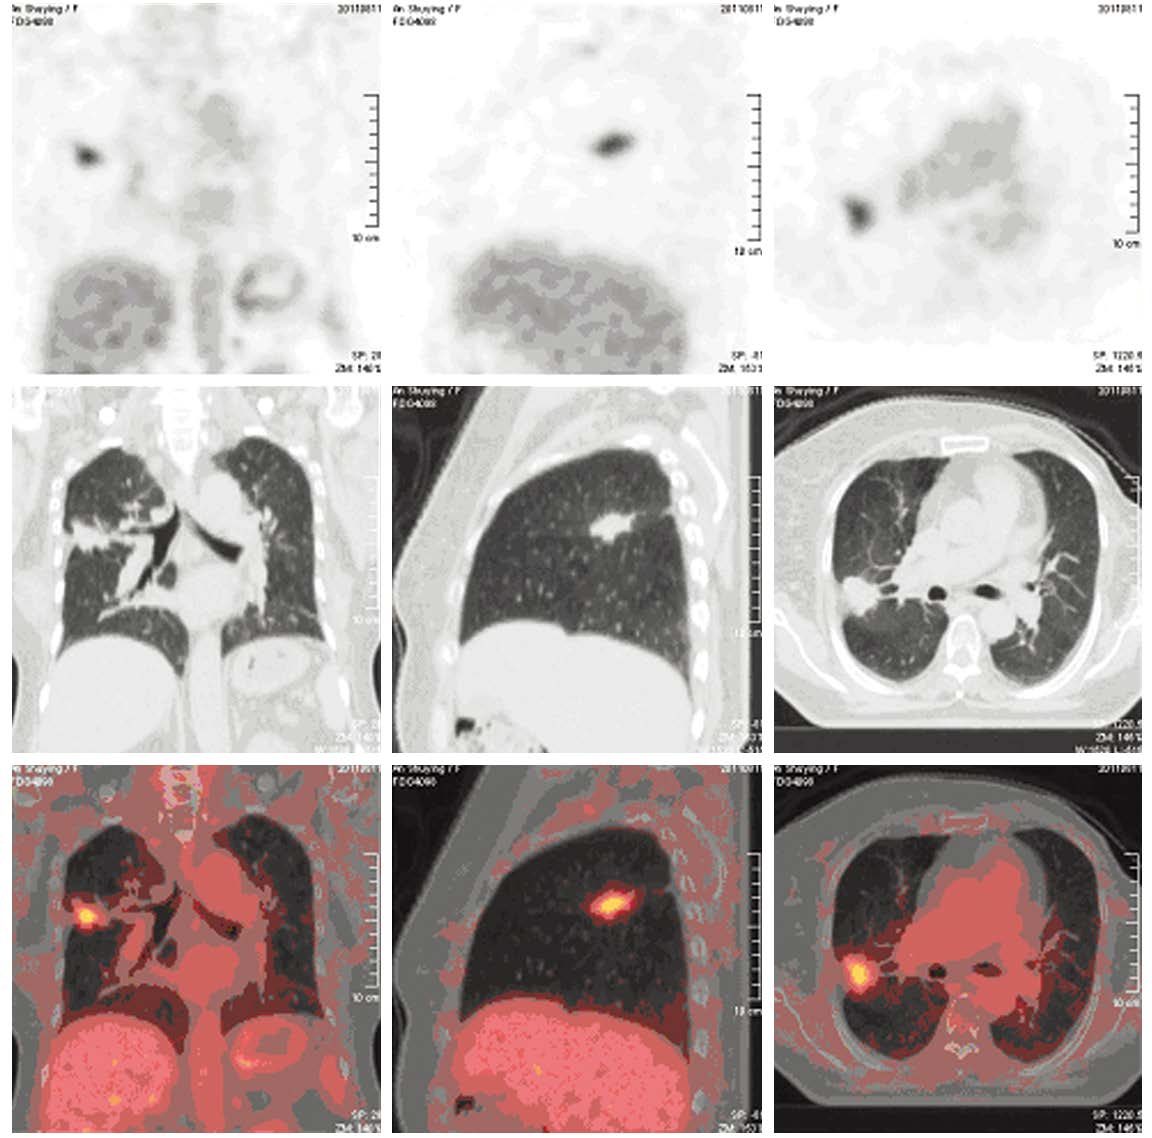

Methods18F-FDG PET/CT images of 56 breast cancer patients who underwent surgery with or without chemotherapyor radiotherapy were acquired in three days to one month after increased serum CEA and(or) CA153 werefound. Diagnoses were made by the consistent comment of two or more doctors after three experiencednuclear medicine doctors reviewed the images retrospectively and independently. And the gold standard ofdiagnoses were the results of either pathology or one-year follow-up.

ResultsOf all 56 cases, there were twocases of local recurrence, 30 cases of metastasis, 14 cases without recurrence and 10 cases of second primarytumor. 18F-FDG PET/CT imaging was positive in 41 cases (one false positive case), negative in 15 cases (twofalse negative cases). The diagnostic efficiency of 18F-FDG PET/CT were: sensitivity 95.24%, specificity92.86%, accuracy 94.64%, false negative rate 4.76%, false positive rate 7.14%, positive predictive value(PPV) 97.56%, and negative predictive value (NPV) 86.67%. The PPV of increased CEA alone, increasedCA153 alone and their combination were 57.14%, 90.91% and 94.12%, respectively (χ2=10.430, P=0.005).

Conclusion18F-FDG PET/CT can be used to identify or rule out the recurrence and metastasis in breastcancer patients with increased serum CA153 and(or) CEA after treatment, with high diagnostic efficiency andgood clinical application value. And it can also suggest the second primary tumor.